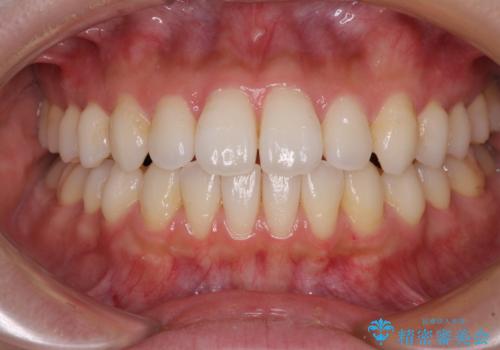

インビザラインで口を閉じやすく

- 下唇に上の前歯が当たることを気にして来院された患者様です。

上顎の親知らずを抜去し、歯列全体を後方に移動させるとともに、IPR(歯と歯の間を削る)を行うことで口元の閉じにくさを改善していくこととしました。

咬合力が強く、マウスピースを介した咬み込みが顕著であったため、奥歯の咬みにくさやIPRのスペースが改善しにくく、治療期間が思った以上にかかってしまいました。